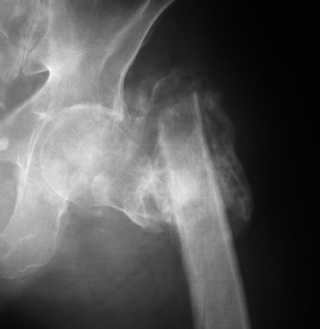

Пациент обратился в институт им. Н.В. Склифосовского 2 месяца назад. При осмотре: левое бедро укорочено на 10 см, нижняя конечность находится в положении наружной ротации 50 градусов, свищей нет. Рентгенологическая картина — рис. 2. При КТ: признаков аваскулярного некроза головки бедренной кости нет, головка находится в ретроверсии (рис. 3).

Имя     : Рис. 2.jpg